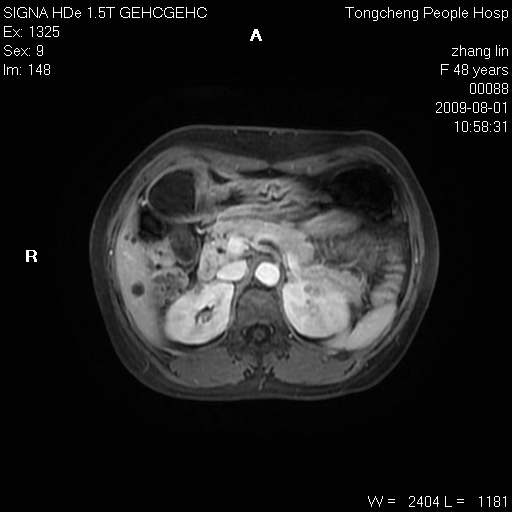

女,48岁。健康体检,彩超发现右肾占位性病变。平素健康。

临床诊断:右肾占位性病变,性质待定(囊肿?肿瘤?)。

上中腹部mr平扫+增强扫描,图像如下:

右肾上极见一类圆形病灶,t1wi呈等信号t2wi呈等高混杂信号,三期增强无强化,边界清---考虑囊肿出血。

同反相位均表现为等信号,病变无强化,考虑含蛋白的囊肿可能,弥散加权相或许有些帮助,

慢性胆囊炎